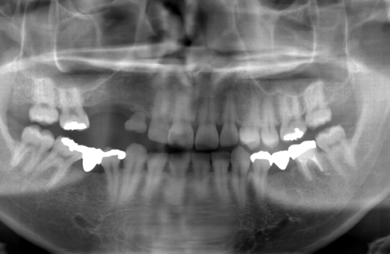

| 性別/年齢 | 男性 / 29歳 | ||||||||||||||||||||||||||||||||

| 主訴 | 右上の歯のない部分に歯を入れたい。 | ||||||||||||||||||||||||||||||||

| 治療方針 | ソケットリフト法により上顎洞底部を挙上することにより、骨の無い部分に骨をつくってあげ、インプラント治療を可能にする。 | ||||||||||||||||||||||||||||||||

| 治療内容 | インプラント3本(ソケットリフト+GBR)、ハイブリッドセラミック3本 | ||||||||||||||||||||||||||||||||

| 総治療費 | 1,264,800円 | ||||||||||||||||||||||||||||||||

| 治療期間 | 7ヶ月 |